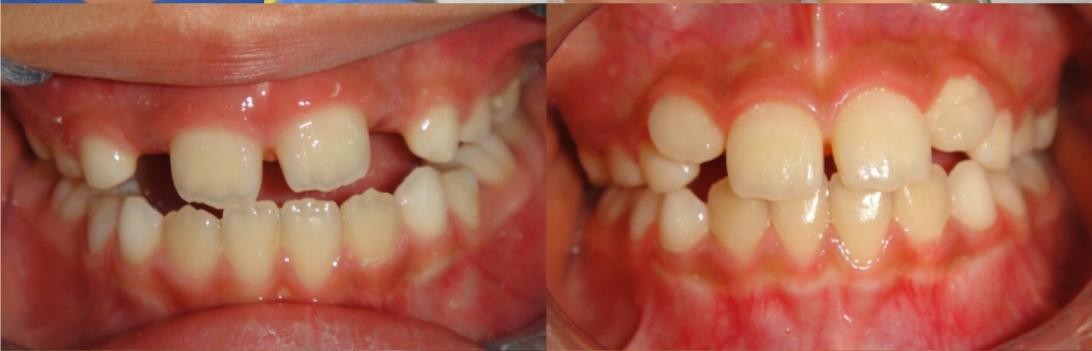

患儿的面像、口内情况如图所示。

可以看到患儿的下巴是偏斜的,面部不对称。经检查发现患儿口内可见多颗乳磨牙龋坏,有偏侧咀嚼习惯,存在颌骨发育的不对称。这种严重的骨性畸形需要双期矫治。第一期早期矫治,其目的是去除病因及干扰因素,让上下颌骨的生长导向正常,从矢状向、横向、垂直向去改善上下颌骨的不调。该患儿首先应用的是矫形力矫治器(螺旋扩弓器),协调上下颌骨宽度,去除锁合侧咬合干扰,建立双侧后牙咬合,治疗乳磨牙龋坏,同时指导患儿用双侧咀嚼食物促进咀嚼肌平衡发育。然后应用的是FRⅢ功能矫治器,解除前牙反合改善下颌偏斜,FRⅢ的作用原理是去除导致颌骨畸形的功能因素而且可以改善轻度的骨性错合。

下图为早期矫治前后面型和口内像对比,可以看到矫治后的患儿面型左右基本对称,下牙列的偏斜程度也明显改善,前牙的反合得到解除,去除了上颌骨发育的不利因素。接下来就是等待患儿换完牙以后进行二期治疗,二期治疗可以从三维方向上控制牙齿的移动方向,进一步平衡咬合,使得矫治效果更加稳定。二期治疗的矫治器可以选择固定矫治器也可以选择无托槽隐形矫治器。